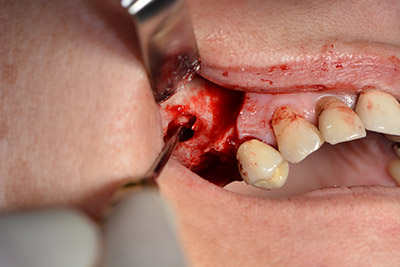

Surgical procedure for implantation

The classic incision (crestal, buccal relief) and the preparation of the mucoperiosteal flap enabled a good overview.

Sky implants (bredent) were used this case. The surgical protocol of these, specify pilot drilling at about 1200 rpm (Fig. 9).